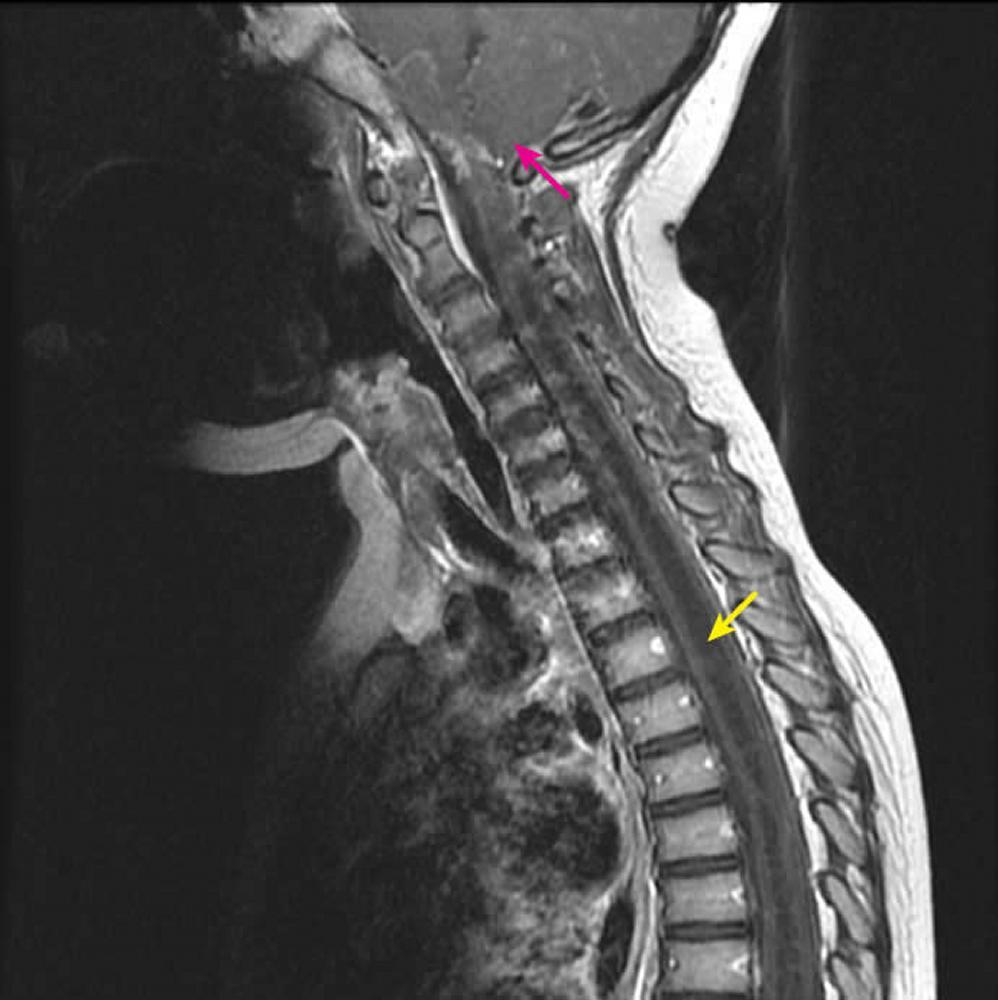

A syrinx is a fluid-filled tubular cavity in or close to the central canal of the spinal cord

What investigation would you consider doing in someone with suspected syringomyelia?

MRI - shows syrinx